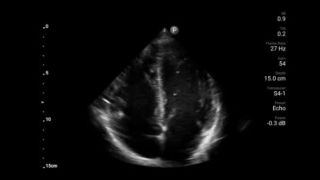

Actúe más rápido para proteger el corazón de sus pacientes

Cuando los segundos cuentan, el ultrasonido portátil puede marcar la diferencia. Lumify puede proporcionar las imágenes de alta definición que requiere cuando y donde las necesite.

Transductor de disposición en fase de banda ancha Lumify S4-1

Oportunidad de revertir potencialmente la miocardiopatía

Introducción a la ecocardiografía transtorácica